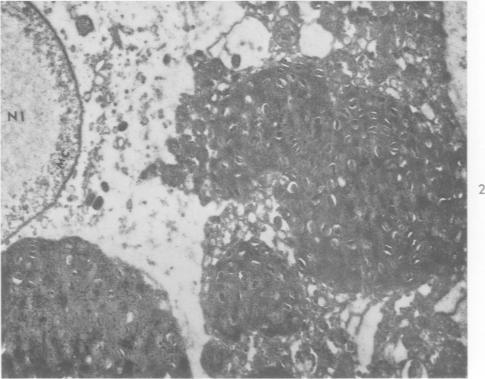

Electron microscope studies of cells infected with the salivary gland viruses.

Ann N Y Acad Sci. 1959 Jul 21;81:133-44. doi: 10.1111/j.1749-6632.1959.tb49302.x.